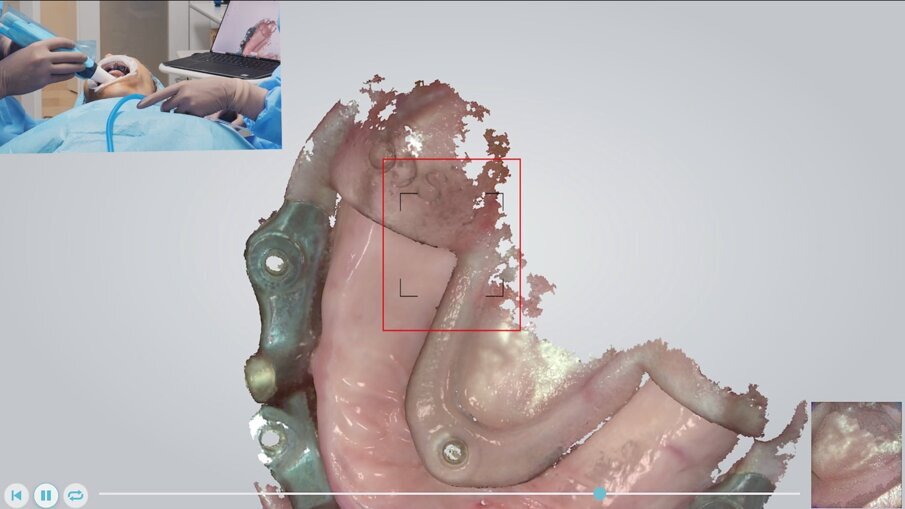

Fase chirurgica Entrando nel vivo delle fasi chirurgiche, vediamo in Fig. 9 l’alloggiamento dell’indice di posizionamento per il fissaggio della dima base. È molto importante effettuare un primo try-in prima dell’anestesia così da accertare il corretto alloggiamento della protesi su tessuti privi di gonfiore. Dopo l’anestesia si procede a verificare nuovamente la posizione andando a comprimere le zone dove può essersi accumulato liquido anestetico. Verifichiamo il corretto alloggiamento del sistema Pcube attraverso le finestre di ispezione e verificando l’intercuspidazione con l’arcata antagonista. Rimosso l’indice di posizionamento (Fig. 10) possiamo apprezzare l’ampio accesso al campo chirurgico offerto dalla dima base e procedere con la fase di scansione intraoperatoria (Trios 4 – 3Shape). Abbiamo infatti deciso per fini documentali di procedere a una serie di scansioni per verificare in modo continuativo l’effettivo grado di precisione del trattamento rispetto alla pianificazione digitale grazie alla sovrapposizione dei file .stl (Fig. 11). Procediamo quindi con il fissaggio della dima chirurgica in titanio anodizzato, sempre sfruttando i sistemi di ancoraggio della dima base (Fig. 12). L’utilizzo di un mucotomo è il passaggio preliminare alla preparazione del sito implantare, non prevedendo, in questo caso, l’apertura di un lembo. Questa scelta si lega alla buona disponibilità ossea e di tessuto cheratinizzato della paziente; tuttavia, la finestra di accesso al campo operatorio garantita dalla dima base del sistema Pcube permette approcci a lembo aperto senza prevederne la rimozione (Fig. 13).